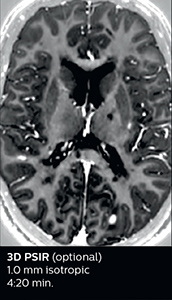

Fast MS protocol with optional sequences

The abbreviated MS protocol for brain is only around 9 minutes, so in case of suspected multiple sclerosis, one or two more advanced sequences may be added, such as PSIR (phase sensitive inversion recovery) or susceptibility-weighted sequences to help us make more confident diagnoses in these inflammatory cases.

In this example, the optional 3D multishot susceptibility weighted sequence with 0.6 mm isotropic voxels is 2 lesions with a central vein sign (arrows) and one lesion with a phase-rim sign (arrowhead). The total scan time, including SmartBrain and axial PD/T2 3mm, is 11:10 min. and is 18:30 min. with the optional 3D PSIR and 3D SWI multishot included.

“In multiple sclerosis patients, we increasingly include a multishot susceptibility sequence [3] in our routine cases, thanks to the shorter scan times. Our abbreviated MS protocol for brain is around 8 to 9 minutes, so we can ask for one or two additional sequences to visualize the central veins, or to get an additional contrast to better depict posterior fossa lesions. In cases of white matter lesions of unknown significance on FLAIR images, for example when we see high signal hyperintensities in the brain, we can add on more advanced sequences such as PSIR (phase sensitive inversion recovery) or susceptibility-weighted sequences to help us in distinguishing between MS and nonspecific or vascular abnormalities in these inflammatory cases.”